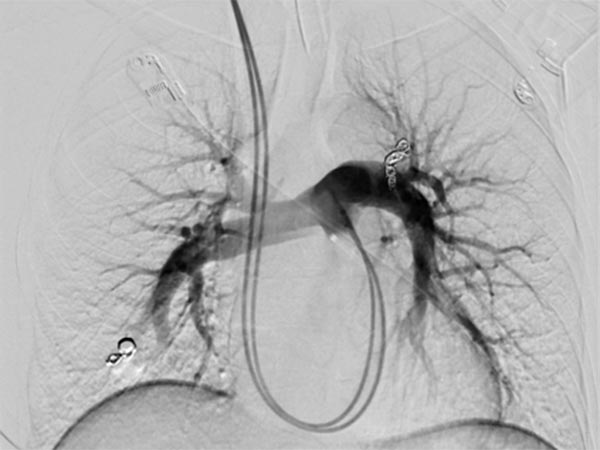

Bei der Abklärung der Grunderkrankung wurde in der Kontrastmittel-Sonographie ein pulmonaler Rechts-links-Shunt gefunden, die Computertomographie bestätigte den Befund mehrerer pulmonaler AVM. Aufgrund der Größe, Indikation zur Embolisation. Die digitale Subtraktionsangiographie zeigt eine bereits superselektiv kanülierte pulmonale AVM im Oberlappen mit der typischen aneurysmatisch erweiterten arteriovenösen Kommunikation.

Über das Herz wurde vom Hals (transjugulär) eine Schleuse in die rechte Pulmonalarterie eingebracht, hierüber ein Koaxialkatheter. Nach Injektion von Kontrastmittel zeigen sich auch im rechten Unterlappen Lungenstrombahn pulmonale AVMs.